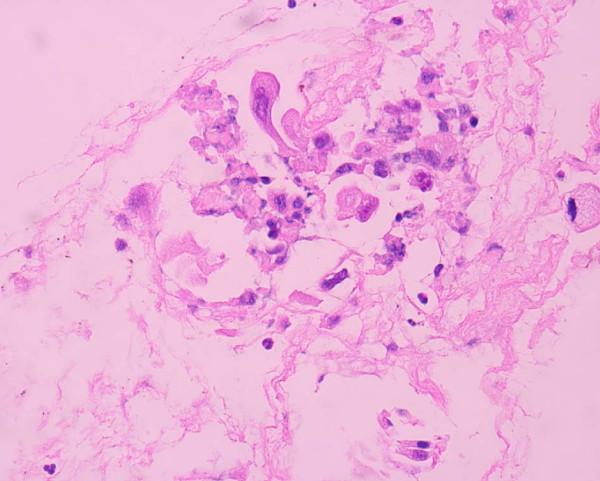

We report the case of a 77-year-old Caucasian male patient who presented initially with a clinical picture of acute cholangitis approximately 2 years after a left lower lobectomy for a low-grade squamous lung carcinoma. CT scan imaging of the abdomen and chest revealed an abnormal growth of the pancreatic head and distention of both the intra- and extra-hepatic billiary tree, whereas osteolytic abnormalities were observed of the 5th left rib, consistent with secondary deposits. Initially an endoscopic retrograde cholangio-pancreatography (ERCP) and sphincterectomy was performed and a plastic stent was placed in the common bile duct to decompress the biliary tree. Cytological examination of the aspirate collected by FNA of the pancreatic lession under EUS guidance revealed cells consistent with a low grade squamous lung carcinoma. Two months later an open cholecystectomy along with a gastrojejunostomy was performed to relieve the patient's gastric outlet obstruction symptoms. Following remission of the patient's attack of acute cholangitis and excessive vomiting he was released from the hospital and instructed to initiate chemotherapy with vinorelbine. The patient succumbed to disseminated disease almost 5 months later.